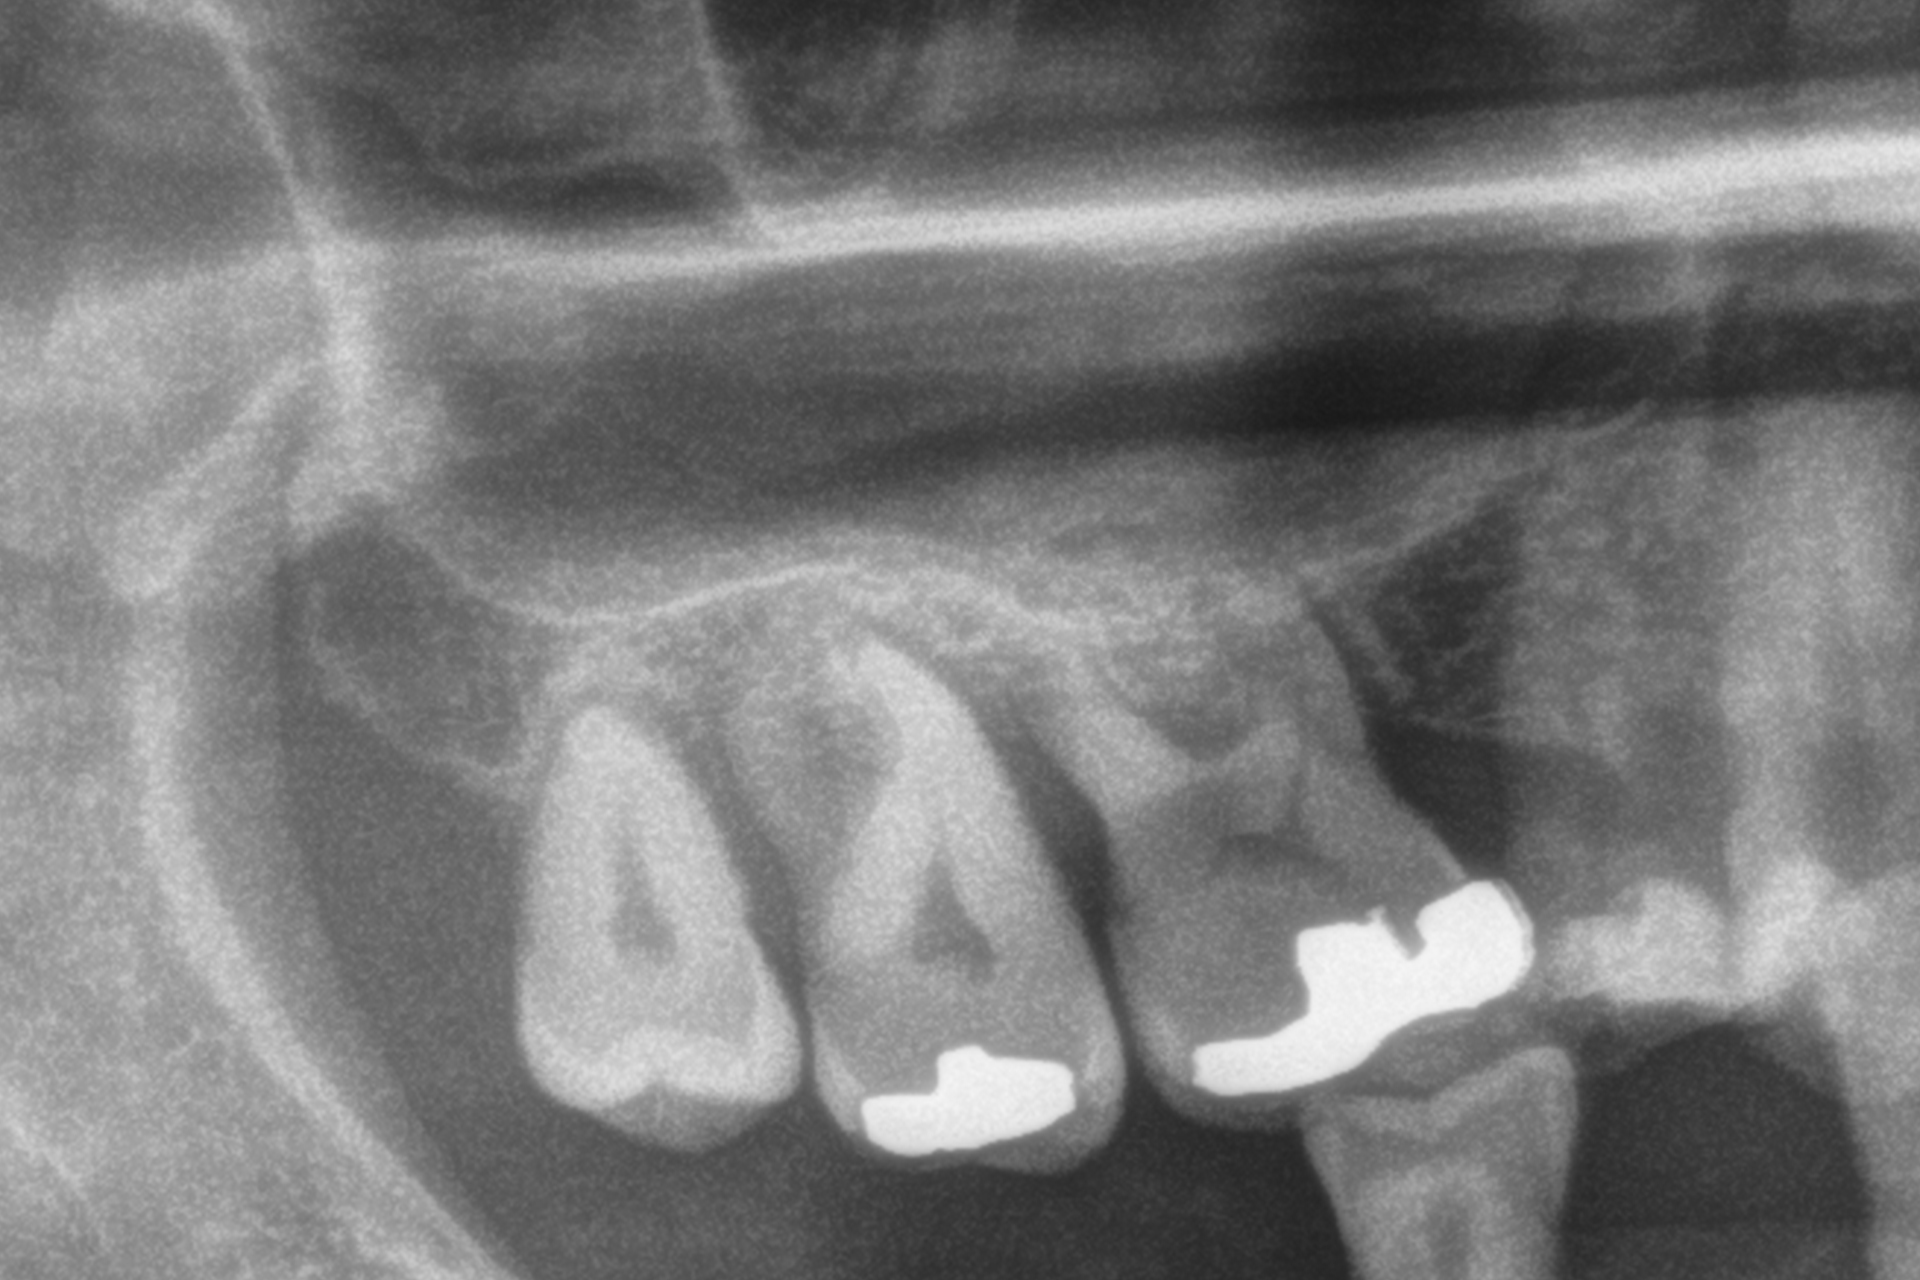

Al termine del follow-up, la perdita ossea crestale media è stata di 0,73 ± 0,18 mm in mesiale e di 0,85 ± 0,34 mm in distale. Alcuni casi clinici rappresentativi sono illustrati nelle Figure 2-10.